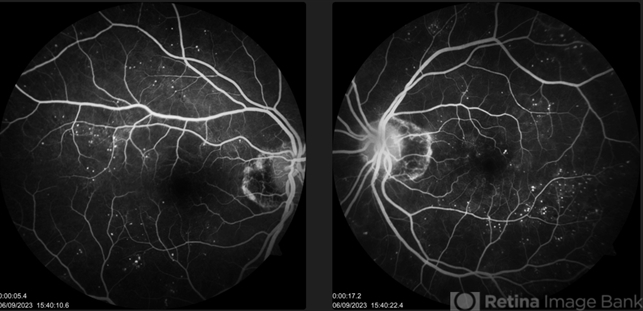

- Diabetic Retinopathy, diabetic macular edema

- 57 year old female with DOV in BE, known diabetic. OU Multiple microaneurysms and haemorrhages at macula with diabetic macular oedema.